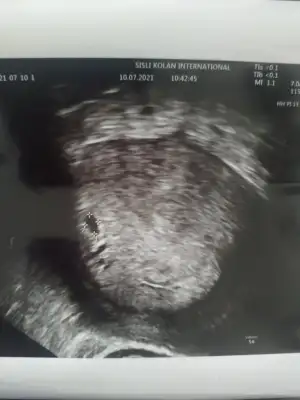

keseyi gördü ama boş tabi daha jkahsdkja salı yine gitcem bayram sonunda da kalp atışını çok rahat duyarız dedi. geç döllenme değil dedi son regl tarihinle uyumlu dedi 4-5 gün sapma var ama o da normal dedi (geç yumurtlamıştım) 6 mart gibi doğum beklerim dedi.. iç tarafta kanama falan yokmuş duvar kısma yapışmış bebecik ama sol tarafta bir kist var o 4 aya kadar erimezse sıkıntı dedi nolcak bilemiyorum. kalp hastası olduğumdan tansiyon sıkıntılı onu beğenmedi salı kardiyolojiyle de bir ortak bakacaklarmış..